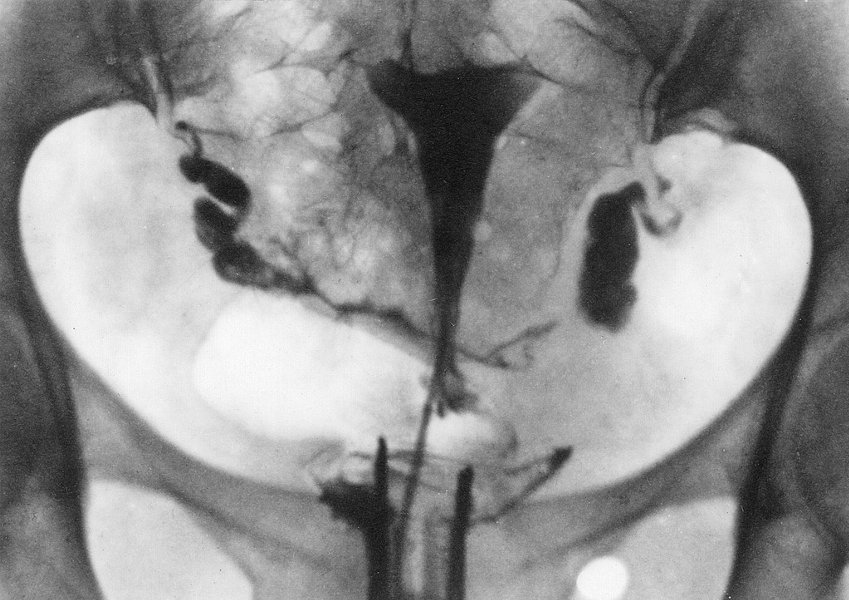

histerosalpingografija (grč. ὑστέρα: maternica + σάλπıγξ: truba, jajovod + -grafija), način kontrastnoga prikazivanja obrisa maternice, jajovoda i jajnika s pomoću rendgenskih zraka ili u novije doba s pomoću ultrazvuka.